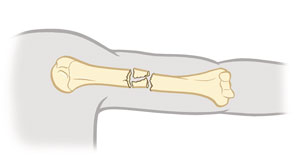

Fractura con desplazamiento

Los fragmentos de hueso no están alineados. Hay un espacio entre los dos extremos del hueso roto.